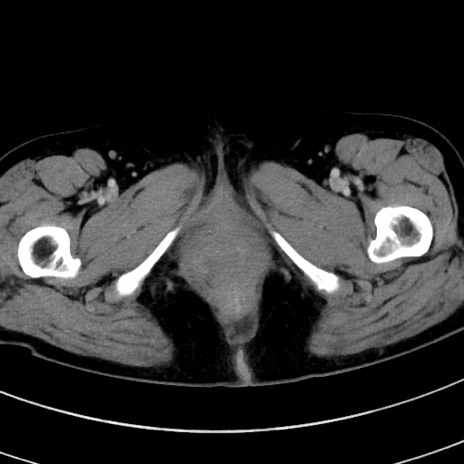

症例9(横断像)

【症例】 60歳代女性

【主訴】むかつき、みぞおちの痛み

【現病歴】3日前よりむかつきがあり、食事がとれない。

【既往歴】糖尿病

【身体所見】発熱なし、心窩部圧痛軽度あるも、腹膜刺激症状なし。

【データ】WBC 7400、CRP 1.92